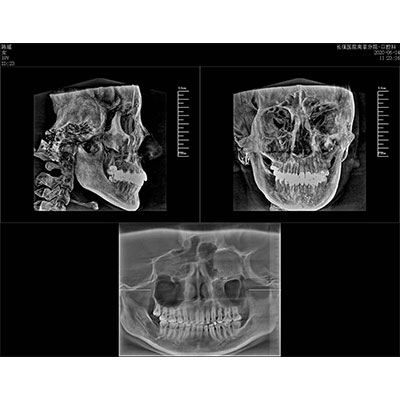

該款牙科CBCT產(chǎn)品采用動(dòng)態(tài)平板探測器,獲得三維圖像的同時(shí)還具有數(shù)字化全景功能,廣泛應(yīng)用于口腔頜面外科、正畸科、正頜外科、種植科、牙體科、顳下頜關(guān)節(jié)科等術(shù)前術(shù)后。

專有三維重建算法,可提供任意位置高清斷層影像。

可同時(shí)觀察軸向面、冠狀面和矢狀面圖像,方便臨床診斷。